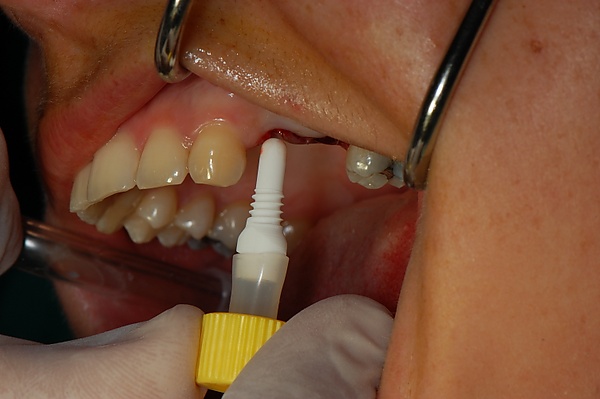

Особое значение имеет уровень гигиены полости рта. Имплантация не может быть выполнена без санации полости рта (все зубы должны быть вылечены), поскольку любой очаг инфекции в организме может свести на нет работу имплантолога из-за высокой вероятности последующего отторжения вживлённого имплантата.

Установка зубных имплантатов может вести к периимплантиту, который возникает из-за бактериальной флоры, попадающей на внешнюю поверхность имплантатов через зубной налет. Лечение данного заболевания проводили корейские исследователи с использованием титановой щетки.

- выполняется профессиональная чистка зубов и имплантов от зубного камня. Гигиена является важнейшим фактором долгого срока службы зубных имплантов.